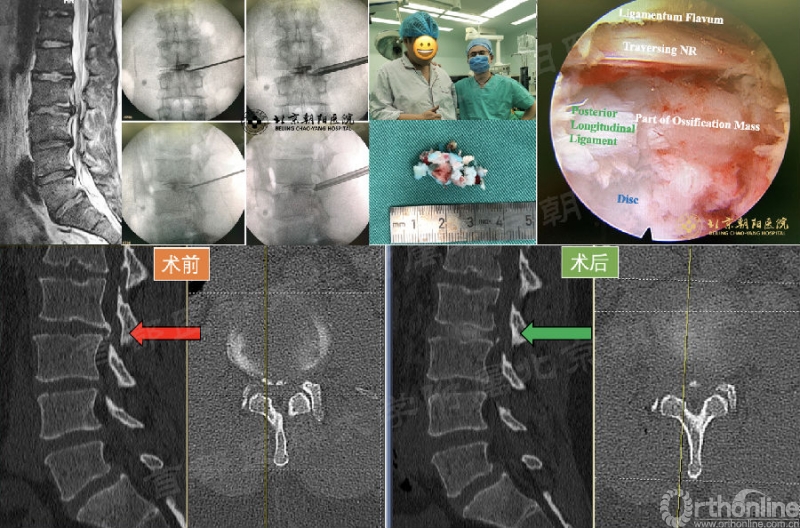

椎间盘突出伴钙化,或椎体后缘离断的镜下减压有一定难度,对技术和手术器械都有较高的要求。以第49例病例为例:

第49例:男,28岁,L2/3(责任节段)椎间盘突出伴钙化。

操作要点:

a、先切除腹侧椎间盘,使骨化“悬空”;

b、镜下骨刀切断骨块两侧,使其“游离”;

c、对于椎体后下缘骨化,将其基底部打断,往下压使其“下沉”;

d、操作空间不足时,退至上关节突,再次扩大成型,豁然开朗。术后患者症状基本缓解。